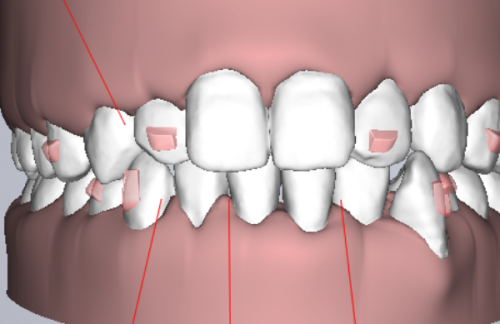

在大型口腔专科医院,科室划分更精细化,会把口腔疾病分为牙体牙髓科、牙周科、口腔外科等,此时蛀牙补牙就可以挂牙体牙髓科,这个科室专门处理牙体硬组织和牙髓的疾病,医生在蛀牙诊断、补牙材料选择、复杂蛀牙处理(比如深龋接近牙髓、牙髓炎前期)上更有针对性,诊疗流程也会更专精。需要明确的是,蛀牙补牙不需要挂口腔外科,因为口腔外科主要负责拔牙、口腔颌面手术、智齿拔除等有创手术类项目,补牙属于修复和保守治疗,和外科范畴无关。